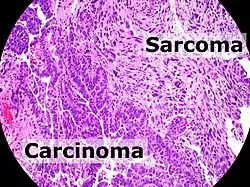

Carcinoma is a malignancy that develops from epithelial cells.[1] Specifically, a carcinoma is a cancer that begins in a tissue that lines the inner or outer surfaces of the body, and that arises from cells originating in the endodermal, mesodermal[2] or ectodermal germ layer during embryogenesis.[3]

The cell type from which they start; specifically:

- Epithelial cells ⇨ carcinoma

- Non-hematopoietic mesenchymal cells ⇨ sarcoma